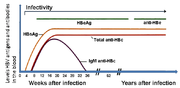

المضاد السطحي لالتهاب الكبد ب (HBsAg) هو الأكثر استخداما للكشف عن وجود هذا المرض. وهذا هو أول مضاد ڤيروسي يظهر خلال العدوى. ومع ذلك، في بداية الإصابة، قد لا يكون موجودا مضاد الڤيروس كما قد يكون غير مكتشف لاحقا من العدوى لأنها تتم إزالته من قبل المضيف. وتحتوى الفيريون المعدية على "الجسيمات الأساسية" داخلية التي تحتوى على الجينوم الڤيروسي. وتتكون الجسيمات الأساسية icosahedral من 180 أو 240 نسخة من البروتين الأساسي، والمعروف خيارياً باسم مضاد الالتهاب الكبدي البائي الأساسي، أو HBcAg. خلال هذه «النافذة» حيث لا يزال المضيف مصاب لكن يزيل الڤيروس بنجاح، والأجسام المضادة IgM لمضاد التهاب الكبد الوبائي ب الأساسي(anti-HBc IgM) قد يكون الدليل الوحيد المصلي للمرض.

بعد وقت قصير من ظهور HBsAg، يظهر مضاد آخر يدعى مضاد التهاب الكبد الوبائي ب e (HBeAg). تقليديا، فإن وجود HBeAg في مصل المضيف يرتبط بمعدلات أعلى بكثير من تكاثر الڤيروس والعدوى المعززة، ولكن لا تنتج المتغيرات من ڤيروس التهاب الكبد المضاد e، ولذلك فإن هذه القاعدة لا تنطبق دائما. خلال المسار الطبيعي للعدوى، قد يتم تطهير HBeAg، وتظهر الأجسام المضادة للمضاد e (anti-HBe) على الفور. ويتبع هذا التحويل عادة حدوث انخفاض هائل في تكاثر الڤيروس.

إذا كان المضيف قادر على التخلص من العدوى، يصبح HBsAg في النهاية غير مكتشف، ويليه IgG الأجسام المضادة للمضادات السطحية لالتهاب الكبد باء والمضادات الأساسية، (anti-HBs، anti HBc IgG).[9] الفترة الزمنية الفاصلة بين إزالة HBsAg وظهور anti-HBs تسمى فترة النافذة. ويعتبر الشخص السلبي لHBsAg لكن ايجابي anti-HBs إما أزال العدوى أو تم تطعيمه سابقا.

الأشخاص الذين يحتفظون بHBsAg إيجابي لستة أشهر على الأقل تعتبر حاملة لالتهاب الكبد باء.[23] وقد يكون حامل الڤيروس مصاب بالتهاب الكبد المزمن، والذي من شأنه أن ينعكس على مستويات مرتفعة من الانين امينوترانسفيراس في المصل والتهاب الكبد، كما يتبين من العينة الحية. أما حاملى المرض الذين ينتقلوا إلى حالة سلبية للHBeAg، لا سيما أولئك الذين اكتسبوا العدوى مثل البالغين، يكون بهم القليل جدا من تكاثر الڤيروس، وبالتالي قد يكون على قدر ضئيل من مخاطر حدوث مضاعفات على المدى الطويل أو لنقل العدوى إلى الآخرين.[24]

يعتبر فحص المستضد السطحي HBsAg هو الفحص الأكثر استعمالاً لتشخيص الإنتانات الحادة بڤيروس HBV وكشف الحملة. حيث يمكن كشفه باكراً منذ الأسبوع الأول أو الثاني وحتى الأسبوع 11- 12 من التعرض لڤيروس HBV، وذلك إذا استخدمت طرق مقايسة حساسة. يدل وجود HBsAg على أن الشخص معدٍ بغض النظر عن كون الإنتان حاداً أو مزمناً.

تتطور الأضداد اللبية Anti - HBc في كل إنتانات HBV، وهي تظهر بعد HBsAg بفترة قصيرة في المرض الحاد، و تدل على الإنتان بڤيروس HBV في وقت سابق غير محدد. تتطور هذه الأضداد بعد الإنتان بڤيروس HBV فقط، أي لا تتطور عند الأشخاص الذين لديهم مناعة لڤيروس HBV ناجمة عن التلقيح. تستمر الأضداد اللبية Anti - HBc بشكل عام مدى الحياة، وهي ليست واصمة مصلية للإنتان الحاد.

تظهر الأضداد اللبية من نوع IgM Anti - HBc) IgM) عند الأشخاص المصابين بمرض حاد عند بداية المرض تقريباً، وهي تشير لإنتان حديث بڤيروس HBV. تكون IgM Anti - HBc قابلة للكشف بصورة عامة بعد 4 - 6 أشهر من بداية المرض، وتعتبر الواصمة المصلية المفضلة للإنتان الحاد بڤيروس HBV. إن سلبية هذه الأضداد مع إيجابية فحص HBsAg في عينة دم واحدة يشير للانتان المزمن بڤيروس HBV.

إن HBeAg واصمة مفيدة، وتترافق بقوة مع عدد جزيئات HBV المعدية في المصل مع خطورة عالية لنقل العدوى (الإخماج).

أما الضد السطحي Anti - HBs فهو ضد مدل محصن، ويشير وجوده بعد الإنتان الحاد عموماً إلى الشفاء والمناعة ضد عودة الخمج. ويمكن أن يكتسب Anti - HBs ايضاً كاستجابة مناعية للقاح التهاب الكبد B أو نقل بشكل منفعل باستعمال الغلوبولين المناعي لالتهاب الكبد HBIG) B). يعتبر وجود 10 وحدات من الضد السطحي على الأقل دليلاً على المناعة، وذلك باستخدام المقايسة المناعية الشعاعية radioimmunoassay) RIA). أما عند استخدام المقايسة المناعية الإنزيمية enzyme immunoassay) EIA)، فإن الإيجابية الموصى بها من الشركة المصنعة يجب أن تعتبر قياساً مناسباً للمناعة. يمكن أن يعبر عن الضد السطحي Anti - HBs أيضاً بالميلي وحدة دولية / ميلي لتر mIU / mL. ويعتبر مستوى 10 mIU / mL دليلاً على مستوى مناعي محصن.